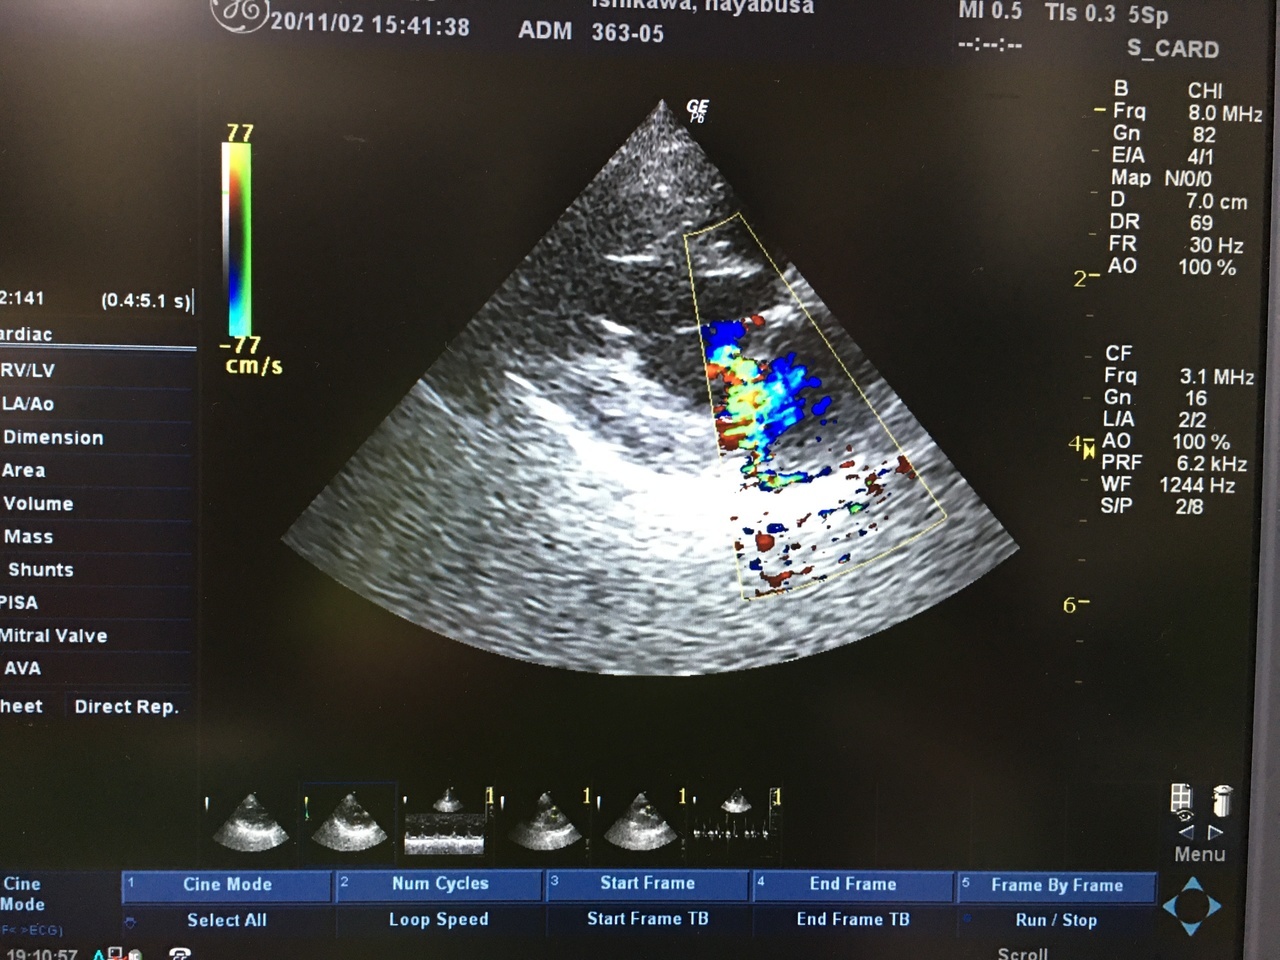

心臓の超音波検査で僧帽弁領域にモザイク像が確認されるかをチェックします